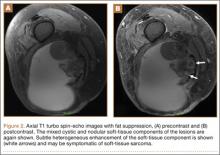

Repeat MRI 2 months later showed increased size of the lesion (9.5×10.5 cm axial, 22.0 cm craniocaudal). Although most findings of a more extensive imaging protocol, including precontrast and postcontrast sequences, were consistent with hematoma, the lesion also had several characteristics that indicated soft-tissue sarcoma. Specifically, findings suggestive of chronic hematoma included the hyperintense short tau inversion recovery (STIR) T1/T2 signal of the cystic component consistent with proteinaceous fluid and the low STIR TI/T2 signal of the periphery consistent with a rim of hemosiderin (Figure 1). Additionally, the cystic component of the lesion had multiple fine septations that are atypical for a hematoma (Figure 1), and several lymph nodes greater than 1.7 cm in short axis were noted in the anterior thigh and hemipelvis that were suspicious of metastatic lymphadenopathy. The encapsulated appearance of the lesion with a sharply defined margin and short transition zone were also reassuring findings for a benign lesion (Figures 1, 2A, 2B). However, several findings were identified that suggested soft-tissue sarcoma, including a nodular soft-tissue component on the medial wall of the lesion that had heterogeneous enhancement with contrast (Figure 2B). We, therefore, proceeded with ultrasound-guided core needle biopsy of the mass and cytologic sampling of the fluid components, which were again consistent with hematoma; no evidence of internal vascular flow was noted on Doppler ultrasound. Ultrasound-guided right inguinal lymph node biopsy was also performed and was negative for malignancy. Because of her large body habitus and pregnancy status, it was agreed that open biopsy should be delayed until after delivery to avoid placing the patient in a prone position.